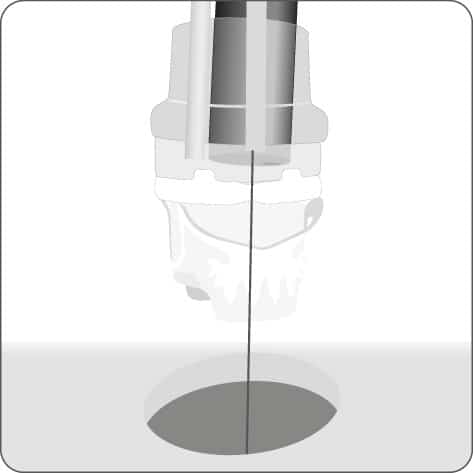

Einführen des Führungsdrahts in den äußeren BARS® Arbeitskanal und Vorlegen in der Anastomose.

Einführen der Anker in den Endoskop-Arbeitskanal und den inneren BARS® Arbeitskanal.